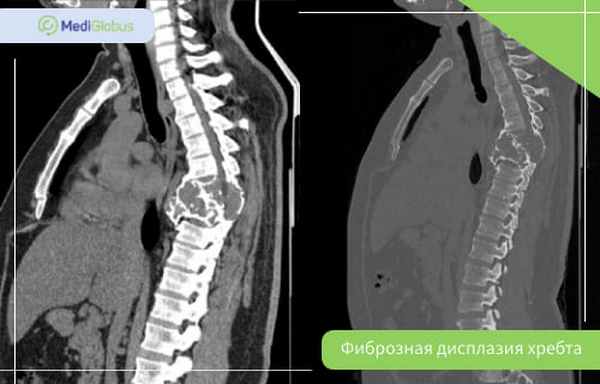

Фиброзная дисплазия позвоночника

Фиброзная дисплазия позвоночника встречается в 2,5% случаев болезни; чаще – в полиоссальной форме. Шейные позвонки поражаются в два раза реже, чем поясничные.

Фиброзная дисплазия хребта может стать причиной сколиоза – бокового искривления позвоночника. В редких случаях из-за поражения позвонков защемляется нерв. В зависимости от того, в каком отделе хребта это произошло, будут отличаться симптомы. Среди них самые распространенные:

Так как главный симптом при поступлении в больницу – это спинная боль, в первую очередь пациентам назначают МРТ и КТ. При подозрении на фиброзную дисплазию могут назначить биопсию, особенно пациентам взрослого или пожилого возраста.

Главные методы оперативного лечения фиброзной дисплазии позвонков следующие:

Во время этой операции хирург фиксирует позвоночник с помощью специальных винтов и пластин для того, чтобы стабилизировать его и убрать компрессию нерва.

Лечение фиброзной дисплазии хребта часто проводится вместе с спондилодезом. Пересадка может проводиться из тазовой кости, или врач может обратиться в банк доноров.